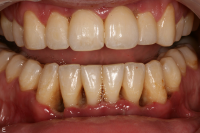

Gingivit är tandköttsinflammation som visar sig genom marginal blödning vid sondering, men där tanden ej har någon förlust av käkbensfäste.

Diagnosen gingivit används vid tänder med marginal inflammation och blödande tandkött, men ingen förekomst av marginal benförlust. Fickdjup 1–3 mm, pseudofickor kan förekomma upp till 5 mm.

Ödematös, rodnad och blödande gingiva.